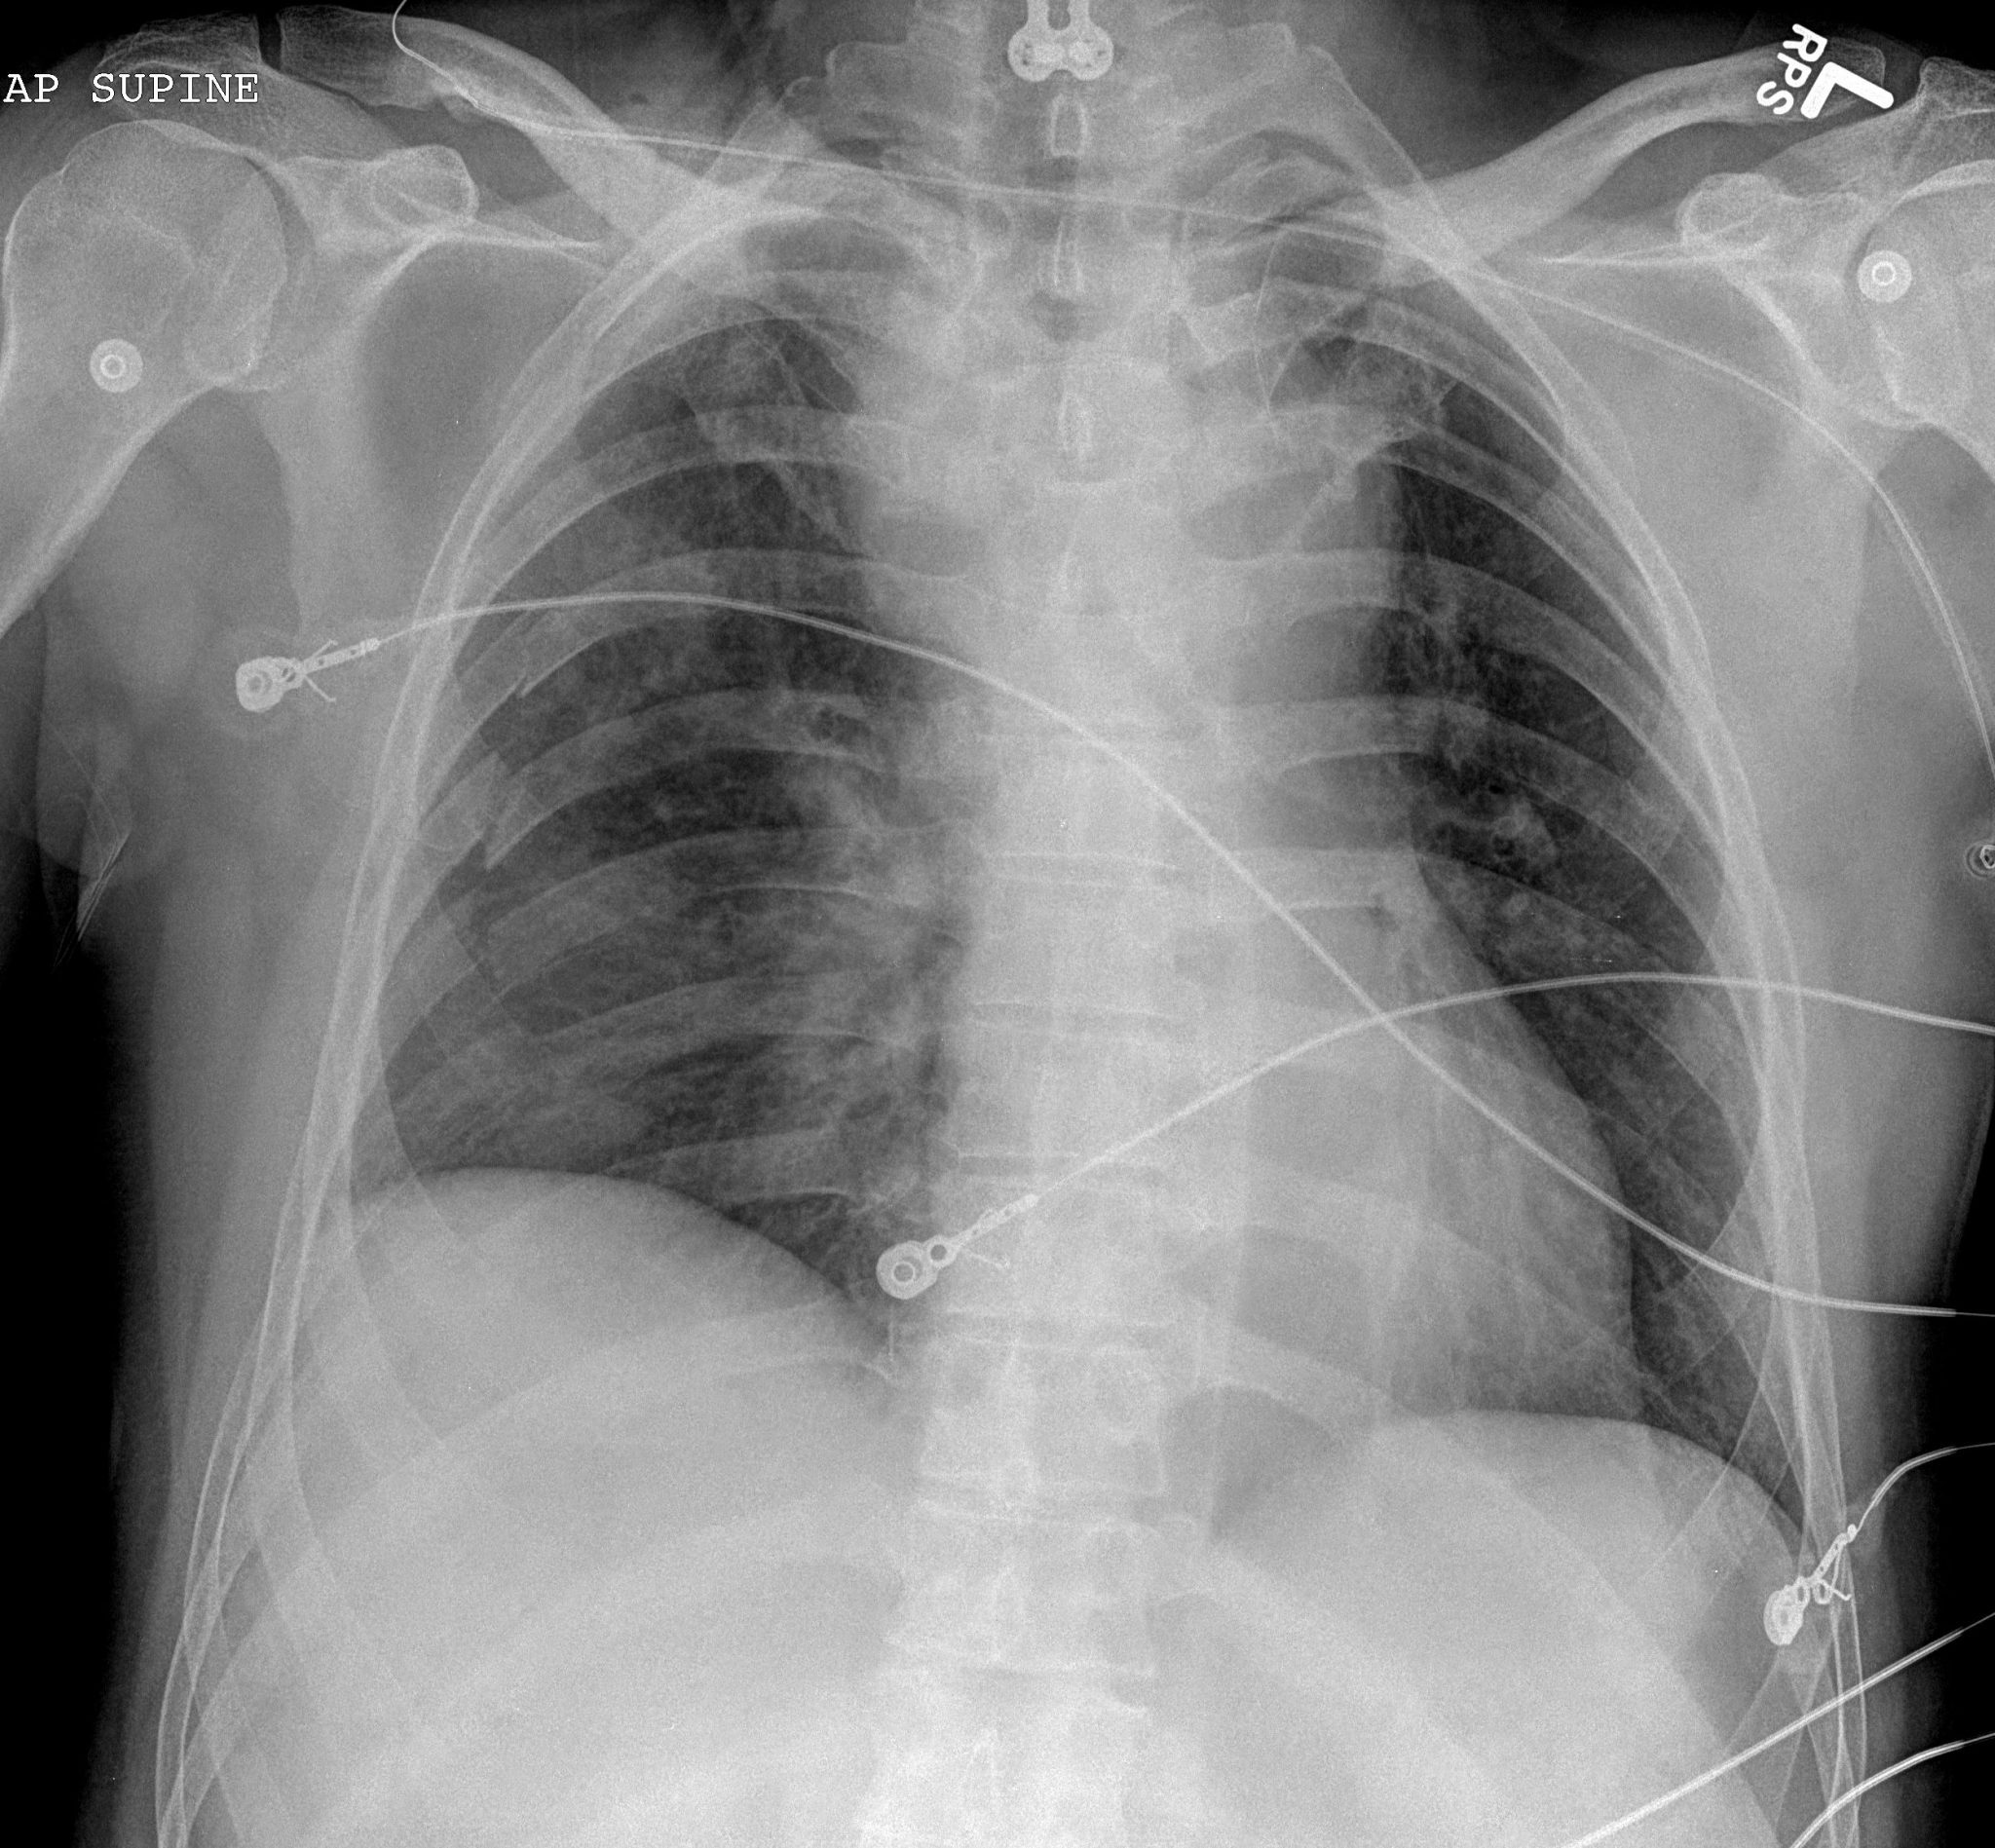

Chest radiograph image from a confirmed COVID19 case demonstrating Chest Radiology Cases learn & practice radiology. Clinical cases and self assessment problems to enhance interpretation skills through ct scan interpretation in clinical. the education committee of the str is pleased to present the case of the month in thoracic and cardiac imaging. Knife penetrates through the lateral left manubrium and extends into the prevascular space. Normal ct of the chest. Chest Radiology Cases.